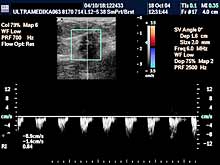

Primenjena tehnika:

- 2D broad band,

- Sono

CT,

- XRes,

- 3D Sono CT,

- Broad band - CD i CPD,

- 3D CPA.